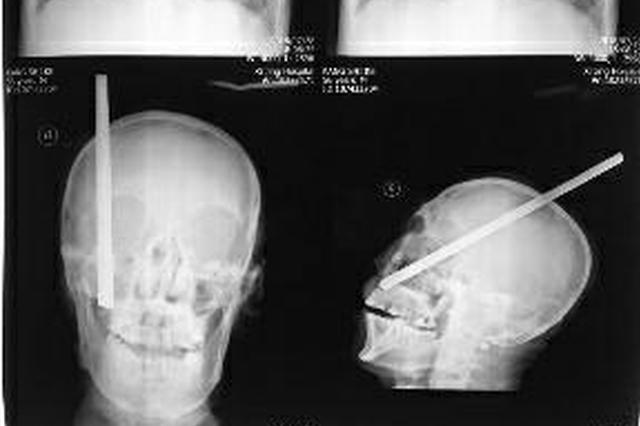

颅内钢筋长达20cm,从头顶部经右侧大脑半球贯穿至右侧面部颅底穿出,钢筋粗大、呈螺纹状,穿过颅内外重要组织结构,贸然拔出极易造成二次损伤。

利用骨瓣成形技术解除头端对钢筋的阻力,顺着钢筋入颅的方向,均匀轻微用力,成功从顶部钢筋入口处将钢筋全部拔出,预计一周左右即可出院,两三个月即可恢复。

直径1.5厘米、长约3米的钢筋扎入农民工头颅。 华商报 图

直径1.5厘米、长约3米,这样一根钢筋从高处坠落,刺穿了56岁农民工康世科的右脑,1个半小时后康世科陷入昏迷,当地医院表示无法救治。危急之下,甘肃消防和陕西医院经过营救大接力,6个小时后便将他送上了手术台,最终从死神手中抢救回了康世科的生命。